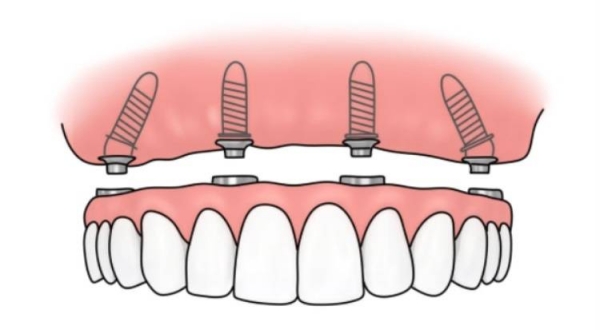

• ALL-ON-4/6即刻負(fù)重技術(shù):僅需4–6顆植體即可支撐整排牙齒,當(dāng)天種牙當(dāng)天吃飯